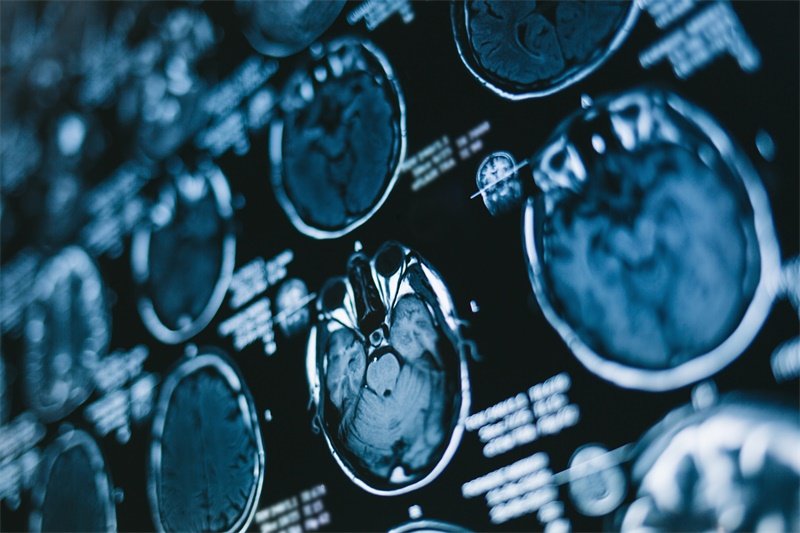

影像学检查

磁共振成像(MRI)是诊断鞍上偏左侧占位空泡蝶鞍的主要工具。这种方法能够提供清晰的脑部成像,通过图像可以观察到区域内的异常结构。

此外,计算机断层扫描(CT)也可以用于评估病变的性质和范围,虽然它的清晰度和细节比MRI略逊一筹。